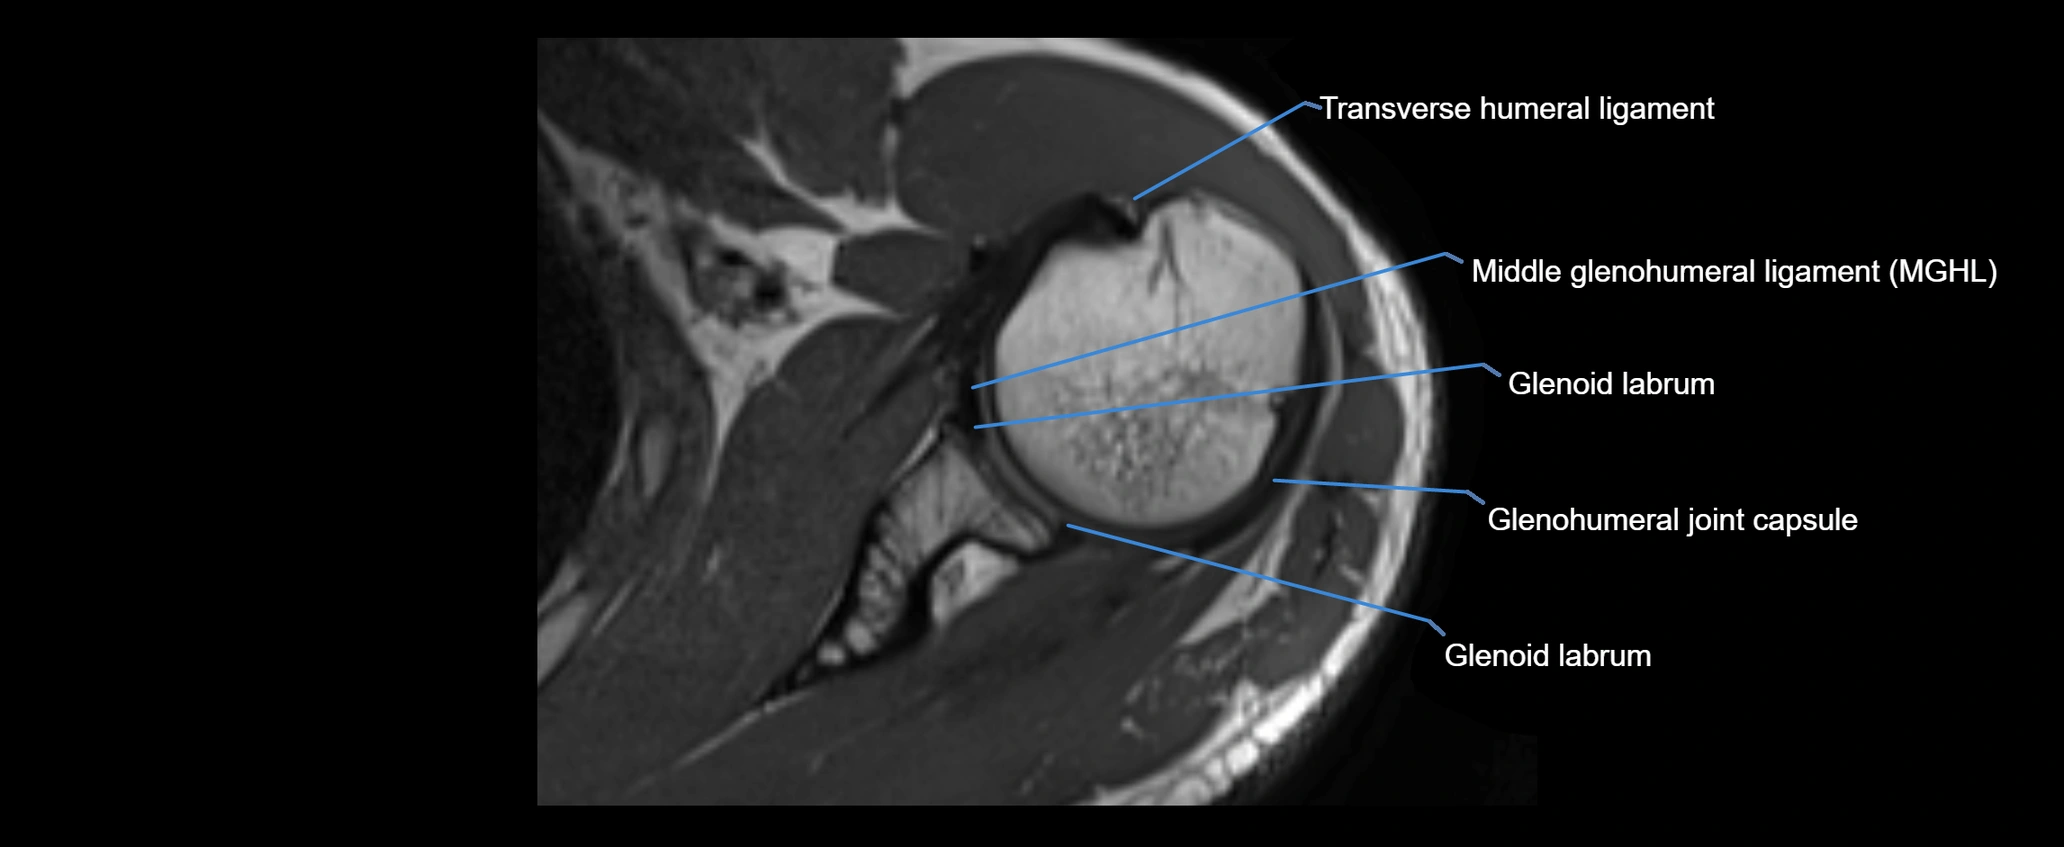

CT image

image